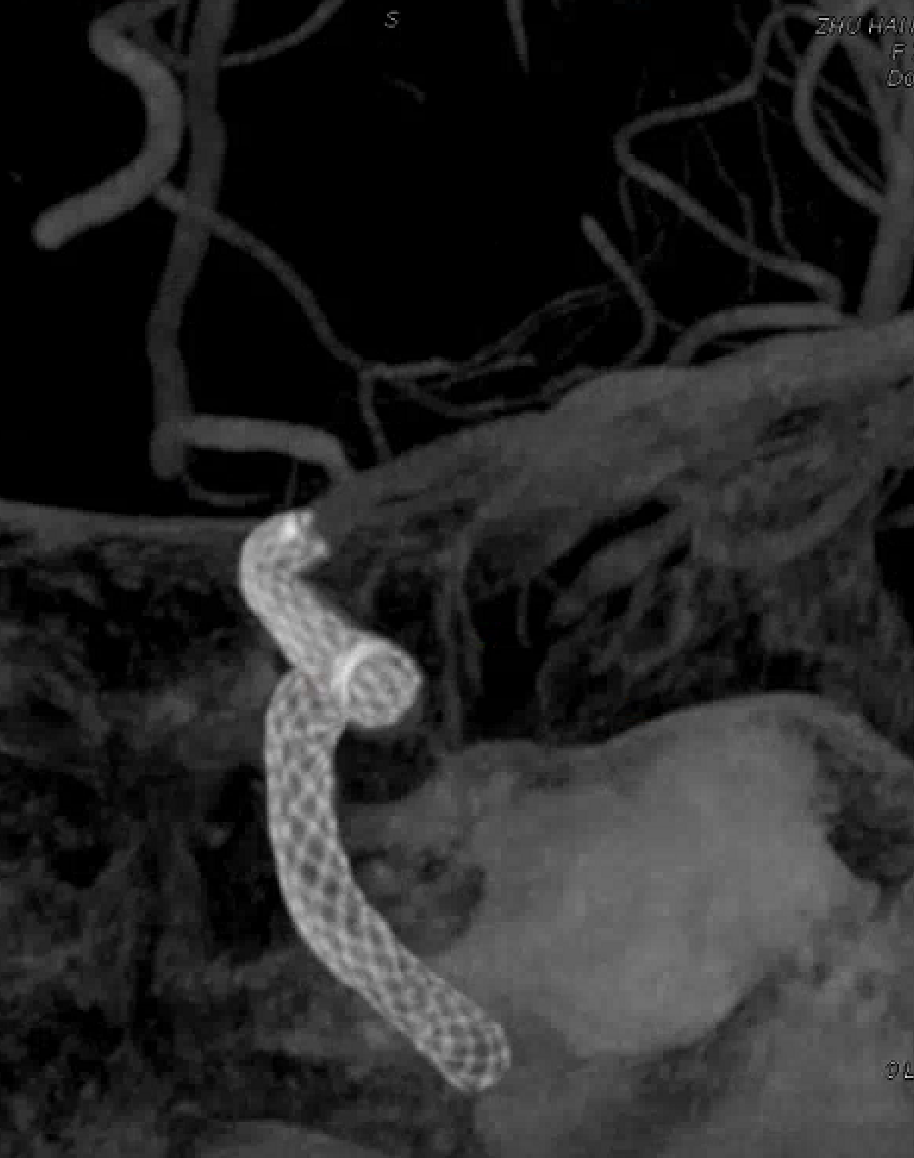

左侧瘤体形态欠规则,4mm×30mm Streamline 优先处理左侧动脉瘤

术后3月复查,瘤体未见显影,载瘤动脉通畅

同期4mm×20mm Streamline 进一步处理右侧动脉瘤